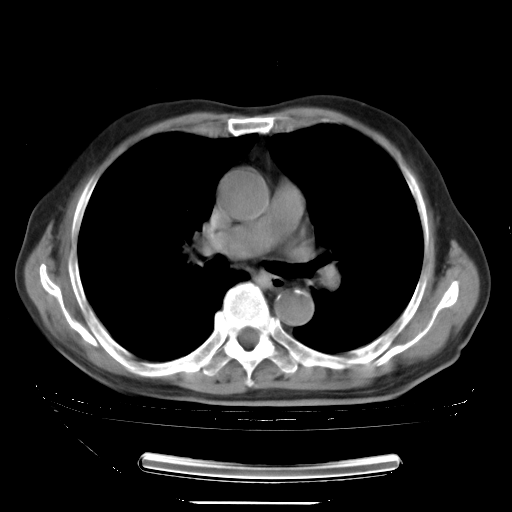

今天复查肺部CT,发现双肺广泛磨玻璃样改变。所以我把3月19日和5月9日相隔50天的肺部CT上传。请大家会诊。

2009年3月19日肺部CT片。

5月9日肺部CT(在4月27日齐鲁医院肺部CT描述部分肺组织磨玻璃样改变,12天后肺组织广泛磨玻璃样改变)

大致读了系列胸部CT:纵隔窗无明显异常,肺窗:从4、27至今:主要是双肺中下野外带可见毛玻璃样改变,目前处于急性肺泡炎阶段,至于原因考虑1、结替组织或胶原血管性疾病所致?2、恶性疾病如恶组在肺部所致的表现或细支气管肺泡癌?3、药物或其它原因如肺蛋白沉着症所致肺泡炎目前不太可能?总之,明天就去请我院的呼吸科、感染科、血液科和临免专家会诊哈。